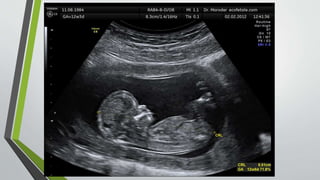

SEGUNDOTRIMESTRE

• Confirmar gestación viable única o múltiple.

• Determinar el sexo fetal.

• Realizar biometría fetal con medición de Diámetro Biparietal, Longitud de

Femur y Circunferencia abdominal.

• Explorar la anatomía fetal y diagnosticar malformaciones.

• Explorar placenta, cordón y líquido amniótico.

• El segundo trimestre va desde la semana 14 a la 26.

• En este periodo ya no se observarán los cambios dramáticos como los que

se mostró durante el primer trimestre.

• En esta Ecografía por el tamaño fetal y por la abundancia de líquido

amniótico, se considera el mejor momento para hacer un diagnóstico

morfológico.